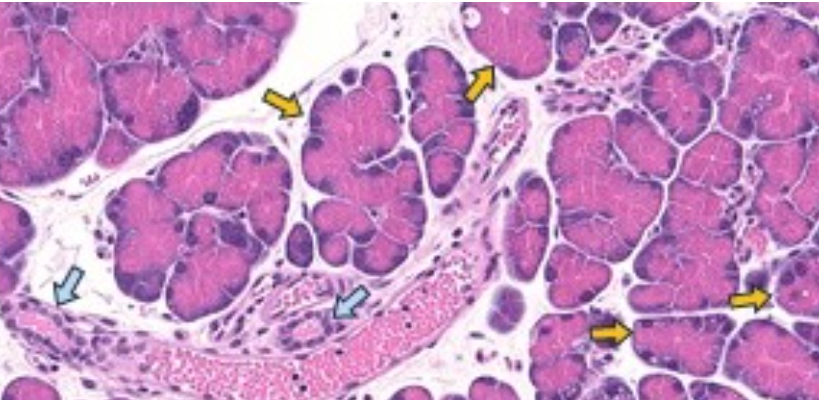

Johns Hopkins Medicine scientists say they have found a pattern of so-called epigenetic “marks” in a transition state between normal and pancreatic cancer cells in mice, and that the normal cells may keep at least a temporary “memory” of those cancer-linked marks.